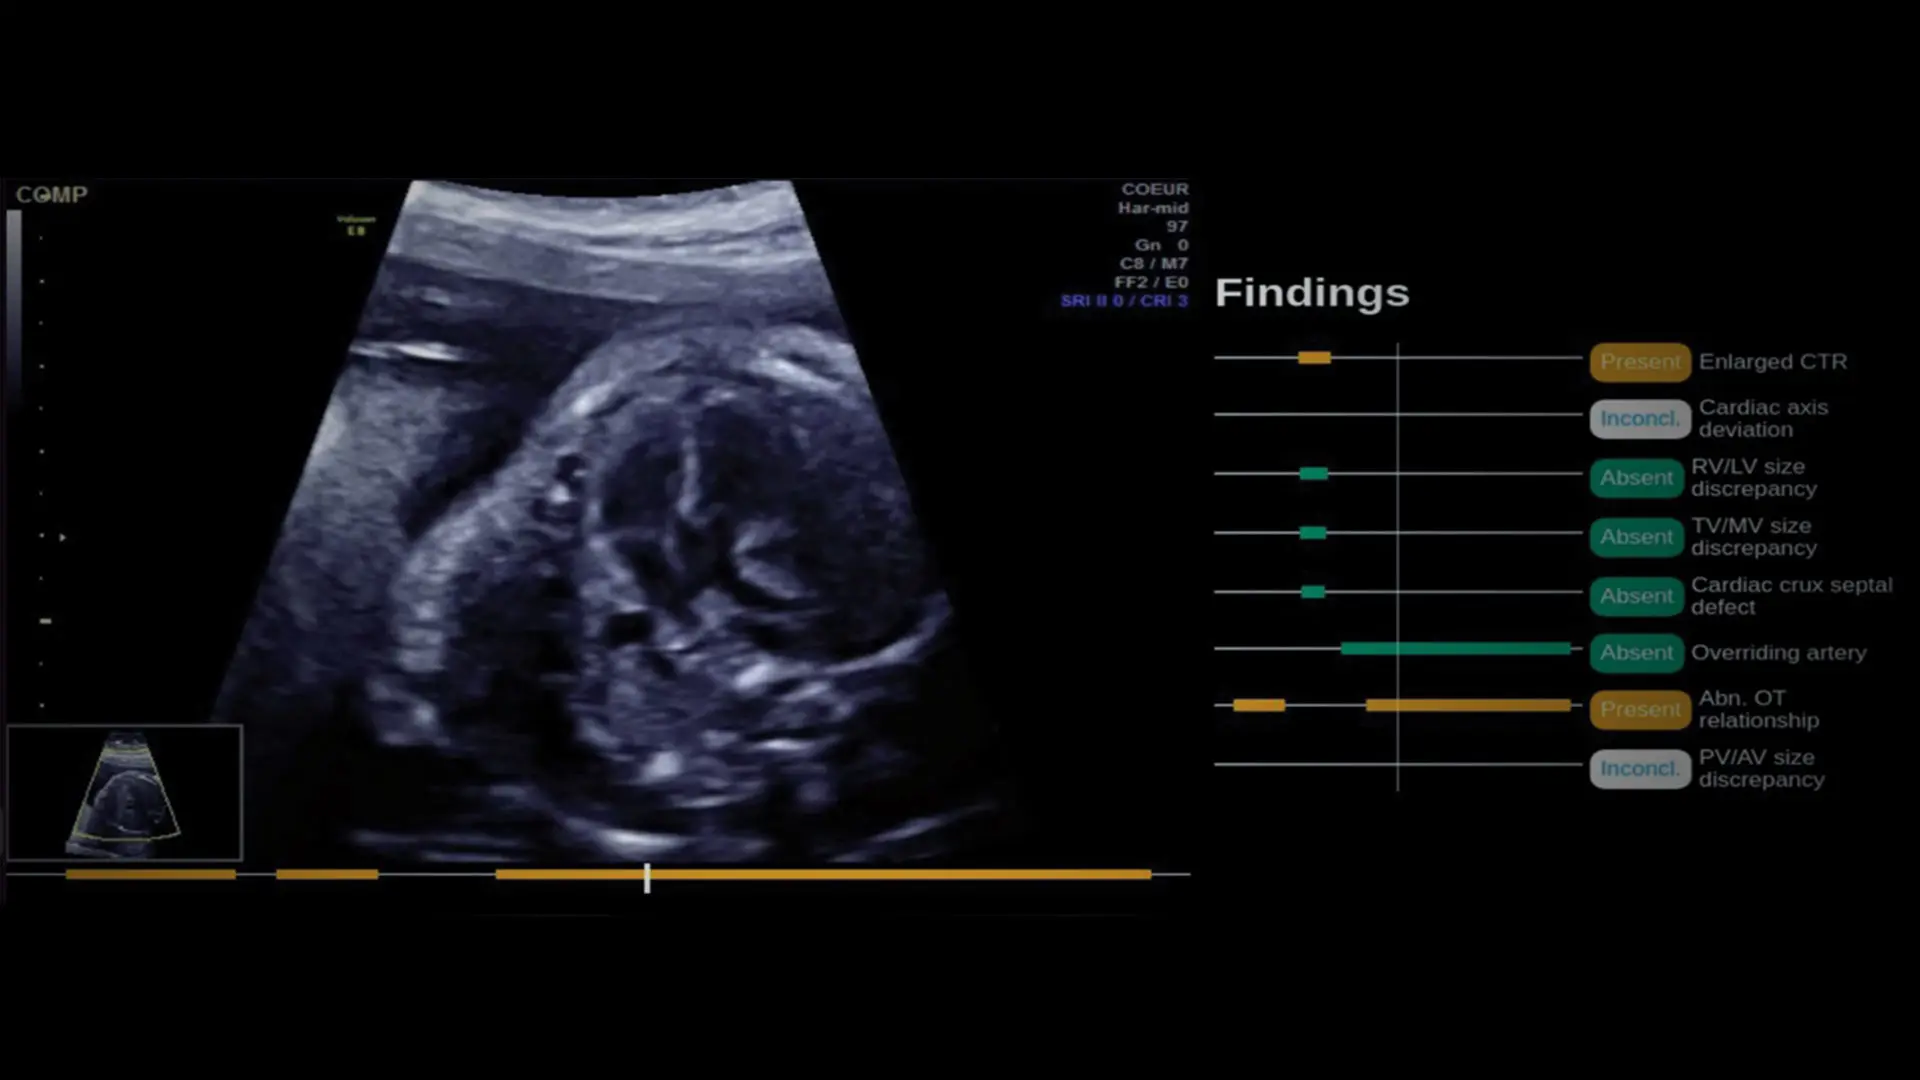

A. In this multireader, multicase study, obstetrician-gynecologists and maternal-fetal medicine specialists interpreted entire second-trimester fetal ultrasound examinations to identify the presence or absence of eight morphologic findings suspicious for severe congenital heart defects (CHDs), along with confidence scores, both aided and unaided by the AI-based software. B. Example annotated cine clip generated by the AI-based software. The AI-based software detects each finding as present (orange), absent (green), or inconclusive (white) and indicates times in the cine clip at when the finding can be seen as present or absent. Vertical bar represents the current frame. CTR, cardiothoracic ratio; RV/LV, right to left ventricular; TV/MV, tricuspid to mitral valve; Abn. OT, abnormal outflow tract; PV/AV, pulmonary to aortic valve.